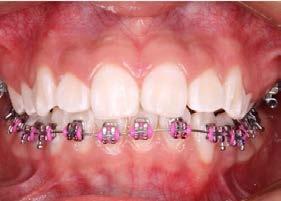

Introducción: Los principales objetivos del tratamiento ortodóncico son corregir las maloclusiones y mejorar la estética dental; sin embargo, el mismo tratamiento puede asociarse a reacciones negativas al requerir aparatología visible que altera aspectos funcionales, estéticos y de higiene oral del paciente. Estos factores podrían influir en la motivación del paciente y determinar una baja adherencia al tratamiento ortodóncico, lo que podría generar retrasos y complicaciones en la estabilización de la oclusión. Objetivo: Evaluar el nivel de satisfacción del paciente con brackets en relación con la higiene oral, el confort y la autopercepción estética. Metodología: Se trata de un estudio transversal con muestreo por conveniencia. Se evaluó el nivel de satisfacción relacionado con la higiene oral, la autopercepción estética y el confort de pacientes tratados en el Instituto mediante un cuestionario validado de autorreporte. Se realizó un análisis descriptivo de la muestra y el cálculo del puntaje del cuestionario; posteriormente, se efectuó un análisis bivariado entre las variables edad, sexo, tratamiento previo y tiempo bajo tratamiento

Higiene oral, autopercepción estética y confort en pacientes con ortodoncia

ortodóncico. Resultados: Participaron 74 pacientes con una edad promedio de 27.1 ± 8.2 años. El 55.4% (n = 41) fueron mujeres. Los hombres presentaron un menor nivel de satisfacción ( = 33.2 ± 6.4) que las mujeres ( = 35.2 ± 8.2). Aquellos pacientes que recibían tratamiento de ortodoncia por primera vez obtuvieron un menor puntaje —y, por tanto, un menor nivel de satisfacción— ( = 33.4 ± 7.6) que quienes ya habían estado sometidos a este tratamiento ( = 35.2 ± 4.6). Los pacientes con hasta 1 año de tratamiento mostraron un menor nivel de satisfacción ( = 33.2 ± 4.6) que aquellos con aparatología por más de 1 año ( = 35.1 ± 3.1). Conclusión: Es importante evaluar, en cada paciente, los factores que puedan influir de forma negativa en su calidad de vida a lo largo del tratamiento, con la finalidad de plantear intervenciones efectivas enfocadas en crear conciencia sobre las expectativas y los posibles inconvenientes derivados del mismo.

Palabras clave: satisfacción, estética, confort, higiene, brackets.

ortodóncico, en el cual se emplean distintos aditamentos con la finalidad de armonizar la oclusión y los rasgos faciales del tercio medio e inferior del rostro.5 A pesar de los beneficios de la ortodoncia, esta puede asociarse con reacciones negativas en los pacientes al requerir, como componente esencial, el uso de brackets o aparatos fijos visibles durante el tratamiento, los cuales suelen dificultar la higiene bucal y acciones como la masticación y la fonación.6

En el estudio participaron 74 pacientes con una edad promedio de 27.1 ± 8.2 años. El 55.4 % (n = 41) de la muestra fueron mujeres. Según las veces que habían estado sometidos al tratamiento, el 62.1 % (n = 46) cursaban por primera vez bajo tratamiento ortodóncico, mientras que el 37.9 % (n = 28) ya habían recibido tratamientos ortodóncicos previos.

Respecto al tiempo bajo tratamiento, el 63.5 % (n = 47) llevaba hasta 1 año bajo tratamiento, y el 36.5 % (n = 27) tenía más de 1 año con aparatología ortodóncica.

Sexo

Los hombres tuvieron un menor nivel de satisfacción respecto a la higiene, confort y autopercepción estética que las mujeres (Tabla 4).

Número de veces bajo tratamiento

Aquellos pacientes que por primera vez recibían tratamiento de ortodoncia tuvieron un menor puntaje, es decir, un menor nivel de satisfacción que aquellos que ya habían estado sometidos a este tratamiento (Tabla 5).

Tiempo bajo tratamiento

En la muestra, el puntaje obtenido fue de = 34.4 ± 5.9. No se encontró diferencia estadística significativa (p > 0.05) entre el nivel de satisfacción y los grupos de edad; sin embargo, sí se detectaron diferencias respecto al sexo, ya que los hombres tuvieron un nivel menor de satisfacción. Esto podría explicarse porque los hombres suelen estar menos familiarizados con el autocuidado y muestran menor tolerancia a los efectos del tratamiento, hallazgo similar al reportado en otro estudio.13

Respecto al número de veces bajo tratamiento, aquellos que recibían tratamiento por primera vez tuvieron un nivel de satisfacción menor que quienes ya habían estado sometidos a tratamientos previos. Esto podría deberse a que los participantes con experiencia previa ya cuentan con expectativas y conocimiento sobre las afectaciones y limitantes que ocasiona el tratamiento.14 Finalmente, los sujetos que llevaban hasta 1 año con el tratamiento mostraron un nivel de satisfacción menor que quienes llevaban más tiempo. Esto podría explicarse por el período de adaptación que debe cursar el paciente una vez aplicado el tratamiento.15